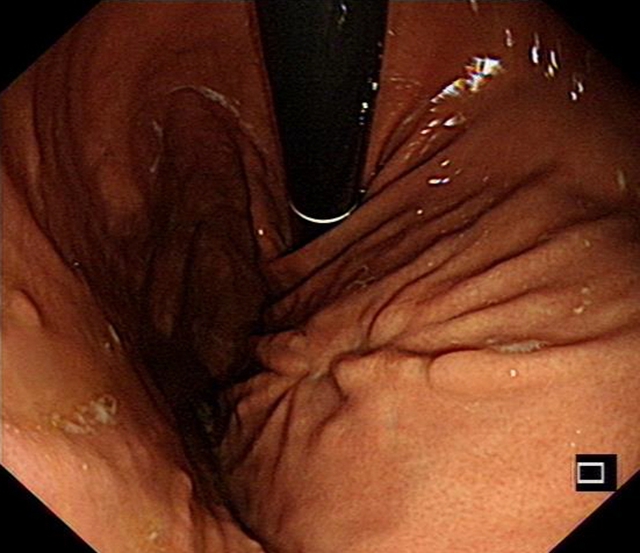

目前,李婆婆饮食恢复正常,无腹痛、腹胀等症状,“与一开始见到的她简直像两个人,在近日的胃镜复查中,她的胃壁已完成愈合,并没有肿瘤的复发”汤小伟副教授说。

术后4月后,患者复查胃镜提示胃内创面已经完全痊愈,肿瘤没有复发。